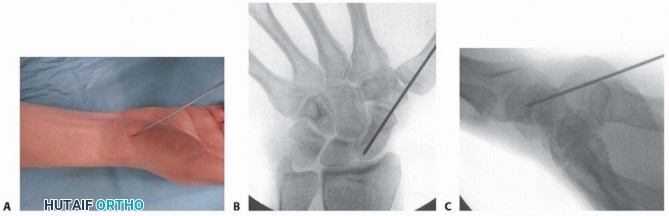

1. ## Volar Percutaneous Approach Position the patient in a supine position with the shoulder abducted and the forearm in supination. The wrist is placed into an extended and ulnarly deviated position over a rolled towel to gain access to the distal pole of the scaphoid. 12 Position the portable fluoroscopy unit such that PA and lateral views of the wrist can be obtained. Image intensification is used to locate the distal scaphoid tuberosity. A small longitudinal stab incision is made at this point, and the soft tissues are bluntly dissected down to the scaphotrapezial articulation. Introduce the guidewire on the distal scaphoid tuberosity. Under image guidance, the wire is advanced toward the center of the proximal pole, aiming for the Lister's tubercle ( TECH FIG 4). The volar prominence of the trapezium may be partially excised to facilitate the correct starting point and trajectory for the guidewire.

*TECH FIG 4 • A-C. In the percutaneous volar approach, the guidewire is inserted into the scaphoid at the scaphotrapezial joint and into the center of the proximal pole. The wire should be inserted aiming for the Lister's tubercle. Alternatively, the guidewire may be placed directly through the trapezium into the scaphoid distal pole. 11 Advance the guidewire to the subchondral bone of the proximal pole. Place a second guidewire of equal length against the surface of the distal scaphoid, adjacent and parallel to the first guidewire. The difference between the lengths of the wires represents the length of the scaphoid. Subtract 4 mm from the length of the scaphoid to obtain the desired screw length. Use the cannulated reamer to ream the near cortex. Insert an Acutrak 2 or mini-Acutrak 2 screw (or a screw from the surgeon's chosen system) of appropriate length, remove the guidewire, and confirm satisfactory screw position and fracture reduction with fluoroscopy. 117 ## PEARLS AND PITFALLS Dorsal Technique Injury to dorsal 1. Blunt dissection through the capsule minimizes the risk of injury. structures Malpositioning of guidewire 1. Pronate and flex the wrist until the ring sign is noted; the center of the ring is the insertion point for the guidewire. Screw penetration 1. Select a screw that is at least 4 mm shorter than the measured length of the scaphoid. 2. A common mistake is to place a screw that ends up too long once the screw compresses the fragments. 3. Confirm central position of guidewire via fluoroscopy. Reduction of unstable fracture 2. Kirschner wires may be used as joysticks for reduction. 3. A derotational Kirschner wire should be placed before reaming and screw insertion if the fragments are unstable. Extremely small proximal pole fractures 1. Use a mini-Acutrak 2 screw to prevent comminution of the proximal fracture fragment. Volar Technique Injury to volar structures 1. Blunt dissection to the scaphoid minimizes the risk of injury. Malpositioning of guidewire 4. A central starting point on the distal scaphoid tuberosity can be hindered by the trapezium. 5. Part of the volar trapezium can be resected to achieve a correct starting point for trajectory of the guidewire, or the wire may be inserted through the trapezium. Screw penetration 1. Select a screw that is at least 4 mm shorter than the measured length of the scaphoid. 2. Confirm central position of guidewire via fluoroscopy. ## POSTOPERATIVE CARE Dressings are applied, and the limb is immobilized in a forearmbased splint, immobilizing only the wrist. The thumb and fingers remain free for range-of-motion exercises. The patient is instructed in the importance of limb elevation and finger range-of-motion exercises. At 2 weeks postoperatively, the sutures are removed, a removable wrist splint is applied, and a wrist range-of-motion exercise program is initiated if fixation is rigid, the fracture is stable, and bone quality is good. If the patient is noncompliant, the fracture is deemed unstable, the fixation is less than ideal, or bone quality is poor, then a short-arm cast is applied for at least 6 weeks. Plain radiographs are obtained at 2, 6, 12, and 24 weeks postoperatively. The splint (or cast) is discontinued when union is confirmed on serial plain radiographs. If there is any question regarding fracture union, a CT scan is obtained. Unprotected strenuous activity or contact sports are not permitted until 3 months postoperatively. Contact sports may be permitted sooner in a brace depending on the type of sport, player position, and quality of fixation. ## OUTCOMES Results of contemporary techniques of percutaneous fixation are excellent; it has been shown to allow for earlier mobilization and return to activity and high satisfaction rates compared to nonoperative measures. 3, 5 , 11, 12, 23, 24, 32 The surgical approach (dorsal vs. volar percutaneous) does not affect the clinical and functional outcome. 11 Use of the transtrapezial approach does not lead to symptomatic scaphotrapezial arthritis at the short- to medium-term follow-u10 Earlier mobilization avoids complications such as muscle atrophy and joint stiffness. Percutaneous techniques result in decreased soft tissue damage compared to conventional open techniques. 32 In a series of 27 consecutive patients, the union rate (confirmed by CT) was 100%. The average time to union was 12 weeks, with a prolonged time to union noted in patients with a proximal pole fracture. 24 ## COMPLICATIONS The risks associated with open reduction and internal fixation, such as damage to the ligamentous support of the carpus and disruption of the dorsal blood supply, are minimized. Possible complications include the following 25: Nonunion Malunion Injury to the dorsal sensory branch of the radial nerve Extensor tendon injury Infection Technical problems: screw protrusion, screw malposition, bending or breakage of guidewire Erosion of the trapezium and discomfort from the head of the screw has been reported with the use of a percutaneous cannulated screw inserted via the volar approach. 32 ## **